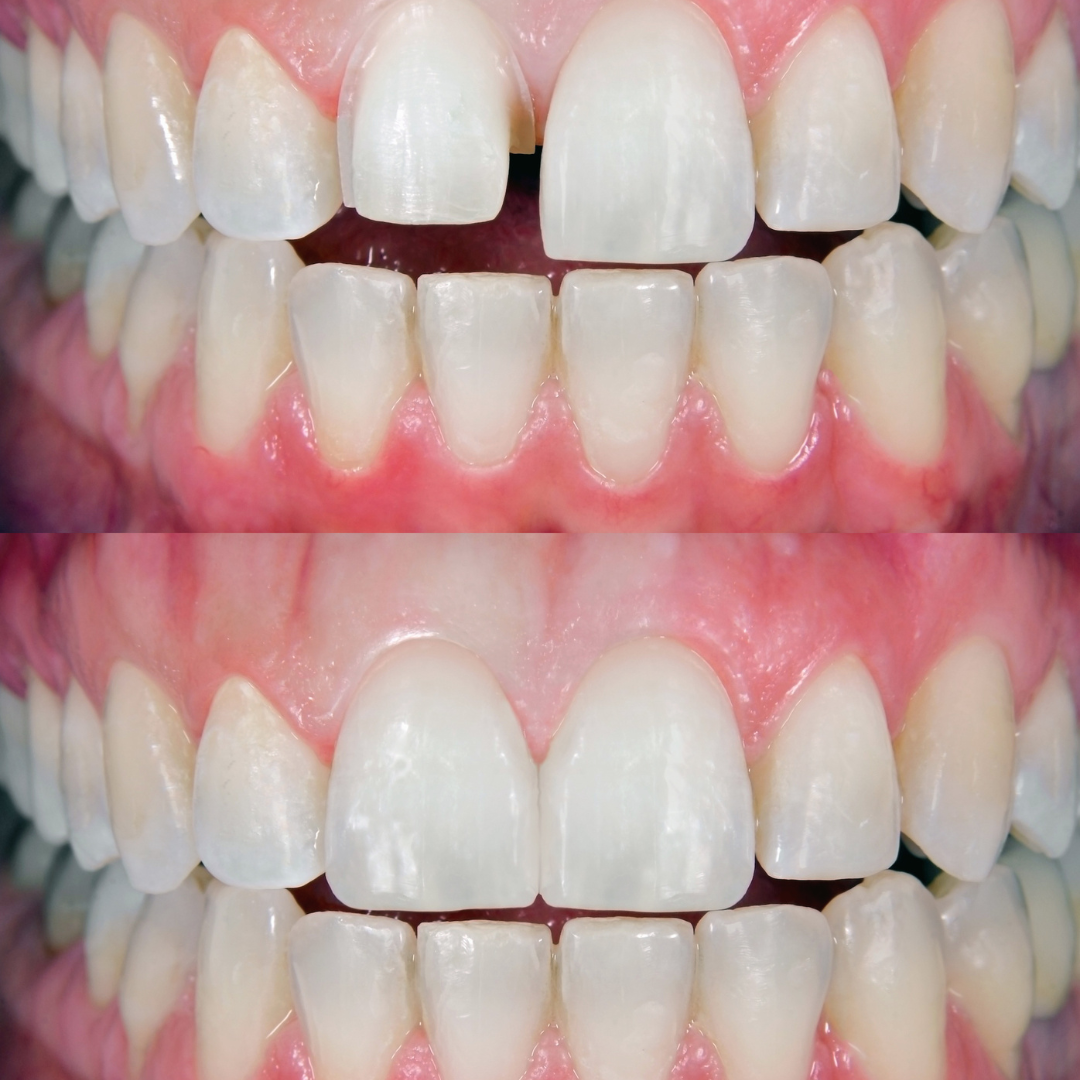

• ভেনিয়ার বা কম্পোজিট ফিলিং: সামনের দাঁত ভেঙে গেলে, এটি ঠিক করার জন্য ভেনিয়ার বা কম্পোজিট ফিলিং ব্যবহার করা যেতে পারে। এটি দেখতে স্বাভাবিক দাঁতের মতোই লাগে এবং দীর্ঘস্থায়ী সমাধান দেয়।

বন্ডিং ট্রিটমেন্ট একটি দাঁতের পুনর্গঠন প্রক্রিয়া!

যা বিশেষ টুথ-কালার রেজিন ব্যবহার করে দাঁতের ফাটল, ক্ষয়, চিপ বা রঙ পরিবর্তন মেরামত করে। এটি দাঁতের ফাঁক বন্ধ করতেও সাহায্য করে।